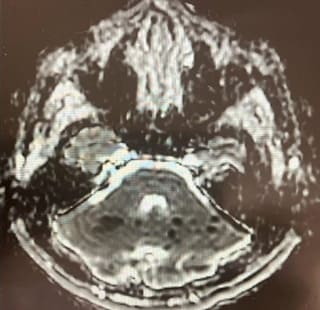

Figure 3: Shows corresponding ADC sequences showing hypointense/ darker regions suggesting acute ischemic infarcts.

We present the case of a 30-year-old previously healthy man who presented to the ER on a Sunday morning with acute onset difficulty breathing and weakness in his extremities. He spent most of Friday and Saturday with friends. Earlier that morning he had complained of neck pain and tingling in his hands, which prompted his roommate to bring him to the ER. He was able to walk into the ER, soon after he required assistance to stand up. He now reported, “I can’t move” and “I can’t breathe, I want oxygen”. This was followed by agitation, respiratory distress (Oxygen saturation at 31%) requiring intubation and mechanical ventilation. There was no history of trauma, recent surgical procedures, diabetes, hypertension, heart disease, other significant past medical conditions, and no recent travel history. His vital signs showed normothermia soon followed by hypothermia returning to normothermia (98-degree F; dropping to 94-degree F and 98-degree F over 3 hours), BP 160/98 (then 116/61; followed by 56 mm Hg systolic that improved with fluid boluses. Heart rate was 66/min and later 36/min improving to 80s (36-137 range); EKG showed alternating sinus rhythm and atrial fibrillation with rapid ventricular rate. On day 2 patient failed extubation due to very low tidal volume (80 ml). Chest CT did not show any pathology to explain respiratory failure. His exam revealed quadriplegia and this led to a neurology consultation. Neurological examination showed intact consciousness; he responded to loud verbal and physical stimulation with nods or head shaking. Eye movements initially showed dysconjugate gaze (this resolved in 24 hours), patient exhibited flaccid (0/5) quadriplegia, areflexia and down-going plantar response. He however managed to dislodge the endotracheal tube (ETT) with his tongue movements multiple times. He had normal sensation in his face; below his neck, he had decreased sensation to temperature and pain, but intact light touch and proprioception. Head CT did not show any acute abnormalities. Other investigations on admission revealed normal CBC, CMP; urine drug screen was positive for THC and negative for stimulants, blood EtOH level was < 3. Additional tests included CSF analysis with cell count of 7, normal protein and glucose. CSF culture later came back negative, and he had a normal sed rate (ESR). Brain MRI revealed numerous subcentimeter bilateral cerebellar, posterior temporal and occipital embolic infarcts (Figure 2 A- 2E and Figure 3). Magnetic Resonance Imaging of the cervical spine showed T2 hyperintensity in the territory of the anterior spinal artery extending from C2 to C6 (Figure 1). MRA of the head and neck were normal (Figure 4A and 4B). Transthoracic Echocardiography showed normal ejection fraction, no intracardiac structural abnormalities and no right to left shunt. Transesophageal echocardiography did not reveal any abnormalities in the proximal aorta. CT angiography of head and neck done few days later was normal as well indicating no occlusions or dissections (Figure 5A-5E). He received 1-gram intravenous solumedrol daily for five days based on initial cervical MRI findings in addition to aspirin started after MRI showed acute infarcts. His CSF also showed 14 oligo clonal bands (unclear significance likely secondary to acute ischemia). Hospital course – On day 3 he went into neurogenic shock and multiple episodes of vasovagal bradycardia (HR in the 40s) and demonstrated hemodynamic instability when he was being moved by nursing staff. His exam now showed intact cognition and normal cranial nerve examination. He developed ileus and had frequent episodes of bradycardia (Figure 6), fluctuating blood pressure all part of autonomic dysfunction causing the nurses to panic. He required transvenous pacemaker which was soon replaced with permanent pacemaker. After four weeks his tidal volume improved from 80 ml to 240 ml., he started to regain significant strength in his lower extremities to the point where he was able to stand up and walk up to 25 feet when his vital signs permitted. His upper extremities remained flaccid, areflexic except for his ability to close his hands to gently squeeze a soft ball. Repeat labs including spinal fluid showed similar findings including 14-oligoclonal bands, normal cell count, protein, and glucose. West Nile virus IgM, HTLV-1, HIV, HSV and CSF VDRL testing were all-negative. After eight weeks, his autonomic instability continued to improve and so did his participation in physical therapy sessions. He could now ambulate up to 100 feet using a special walker; however, he remained flaccid in his upper extremities and continued to need intermittent daily ventilator support due to tidal volume at ~300ml. Repeat MRI of his brain and spinal cord was placed on hold due to his pacemaker that requires many weeks for lead maturation.